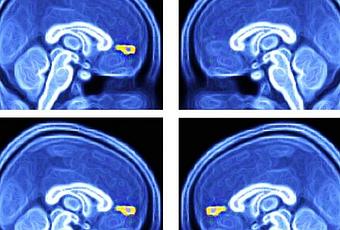

Des scientifiques du Wake Forest Baptist Medical Center (Caroline du Nord) ont mis au point une approche diagnostique simple des troubles du spectre autistique TSA) : l'équipe mesure la réponse d'enfants autistes à différents signaux environnementaux sous imagerie par résonance magnétique fonctionnelle (IRMf). Chez les enfants autistes (visuels du haut) la présentation unique d'objets ou de visages favoris n'active pas une zone spécifique du cerveau, le cortex préfrontal médial ventral. Ce test d’imagerie simple est décrit dans la revue Biological Psychology.

L’équipe a testé la réactivité du cortex préfrontal médial ventral du cerveau (vmPFC : ventral medial prefrontal cortex) aux signaux visuels représentant une interaction sociale « de grande valeur », chez 40 jeunes participants âgés de 6 à 18 ans, dont 12 diagnostiqués avec TSA et 28 suivant un développement normal. Les participants ont passé l’IRMf tout en visualisant 8 images de personnes ou d'objets, chacune plusieurs fois. Chaque série d'images comprenait 2 images choisies de manière individuelle représentant la personne et l’objet préférés de chaque participant. L’expérience montre que la réponse moyenne du vmPFC est significativement plus faible dans le groupe de participants atteints de TSA.

- Le simple recours à des images du patient et à l’IRMf pour capturer 30 secondes de données s’avère donc suffisant pour diagnostiquer l’autisme. « La façon dont le cerveau réagit à ces images est cohérente avec l’hypothèse selon laquelle les cerveaux des enfants autistes ne codent pas la valeur de l'échange social de la même manière que les enfants en développement typique », expliquent les chercheurs.